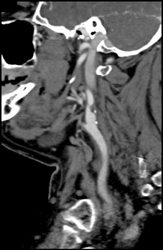

Calcifications in the Aortic Valve